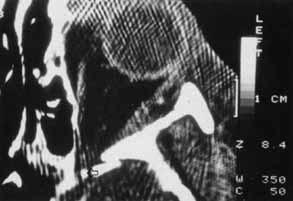

Fig. 12 In this patient (A) with right medial wall and tripod fracture, the mass effect of orbital air (B) (arrow) causes exophthalmos and contributes to hypophthalmos.